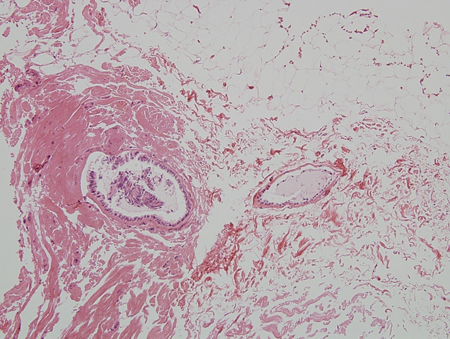

Oestrogen excess or increased oestrogen sensitivity stimulates proliferation of breast ducts and ductal epithelium. If androgen deficiency or androgen inhibition is present, the effect of oestrogen is more pronounced, even if the oestrogen level is normal. At puberty, marked increases in growth hormone, insulin-like growth factor 1, follicle-stimulating hormone, and luteinising hormone drive both oestrogen and testosterone production, but the oestrogen peak precedes the peak in testosterone production. There are many contributors to increased oestrogen versus androgen effect in adults. Regardless of cause, the initial phase with proliferating ducts, ductal epithelium, stroma, and fibroblasts, accompanied by inflammation and oedema, often gives way to a more quiescent stage characterised by dilated ducts, stroma, and fibrosis with little inflammation. The fibrotic stage is far less likely to regress either spontaneously or with treatment. Progesterone levels in men are low, so there is little alveolar tissue in the male breast even when gynaecomastia is present. Hence, galactorrhoea is rare.[Figure caption and citation for the preceding image starts]: Histology: normal male breast; rare, isolated ducts; no lobules; 10X magnificationFrom Minneapolis Veterans Affairs Medical Center pathology collection [Citation ends].

[Figure caption and citation for the preceding image starts]: Histology: gynaecomastia; clusters of ducts, halos of oedema, fibrous background; 5X magnificationFrom the collection of Catherine B. Niewoehner, MD [Citation ends].